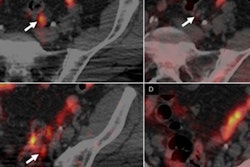

In other news from Europe, Italian researchers recently reported progress with a novel PET imaging agent that targets copper accumulation in tumors. The agent -- copper-64 chloride -- is being evaluated for its ability to detect early prostate cancer relapse.